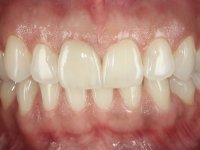

The patient came to the consultation because she did not like the “dark line next to the gums” that she had on her upper right central incisor.

Female patient, 33 years old, non-smoker. Tooth 11 with endodontic treatment rehabilitated with a crown. This crown shows an infiltrated cervical interface. The smile line was high, this area being very visible. The patient had a thick gingival phenotype and good oral hygiene.